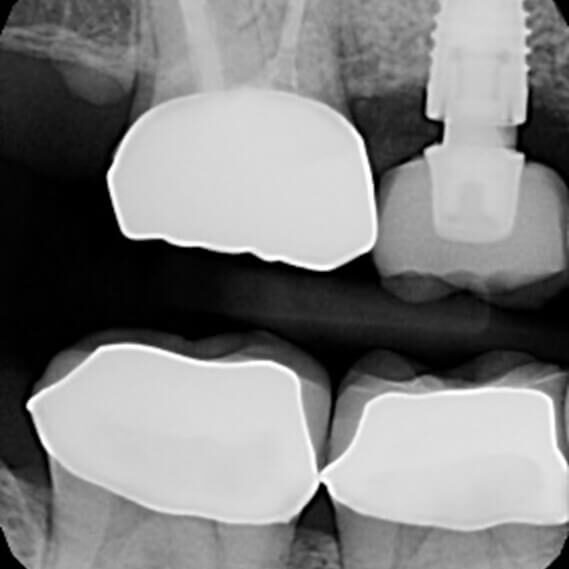

ULTRASONICS: Complications of Abutment Screw Retrieval Secondary to Prior Ultrasonic Attempts

There has been much written on the use of ultrasonics in retrieving fractured screw fragments, which I didn’t think a lot about until May of 2023, as it has not been a part of my fractured screw retrieval algorithm.